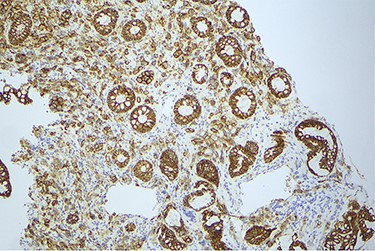

Surveillance colonoscopy in 2018 identified a fungating nonobstructing mass in the sigmoid colon (Fig. 1). Histology from a biopsy showed poorly differentiated carcinoma (Fig. 2). Given the history of breast cancer, further immunohistochemical staining was performed, which was positive for E-cadherin (Fig. 3), ER (Fig. 4), PR, GATA3 binding protein (GATA 3) (Fig. 5) and negative for Cytokeratin 20 (CK20) (Fig. 6). This confirmed metastatic invasive ductal carcinoma of breast. A positron emission tomography (PET) scan showed only the retroperitoneal mass involving the proximal sigmoid colon with no other evidence of metastatic disease (Fig. 7).

Histology slide showing positive immunohistochemical staining for E-cadherin.